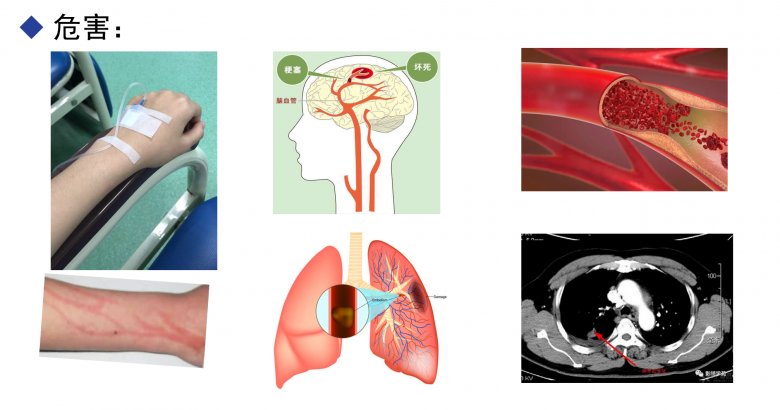

注射劑中的不溶性微粒是指藥品在生產(chǎn)或使用過程中經(jīng)由各種途徑產(chǎn)生或混入的微粒性雜質(zhì),粒徑在1~50 μm、肉眼不可見,但因其可隨血液流動卻不能被代謝而可能對人體造成難以發(fā)現(xiàn)和潛在的嚴重危害。20世紀(jì)30年代起研究人員開始認識到不溶性微粒的危害,并于60、70年代間對此開展了大量的實驗及臨床研究,隨后不溶性微??刂票患{入注射劑質(zhì)量標(biāo)準(zhǔn),且其檢測方法得到不斷改進?,F(xiàn)在,有關(guān)注射劑中不溶性微??赡軐θ梭w造成危害的觀念已為臨床廣泛接受,過敏反應(yīng)、靜脈炎、血管栓塞、微循環(huán)堵塞、動脈硬化、熱原反應(yīng)、肉芽腫、肺栓塞等多種與不溶性微粒有關(guān)的不良反應(yīng)都會引起醫(yī)護人員的重視。

不溶性微粒的傷害

《中國藥典2020版》對注射劑中不溶性微粒的控制要求僅限于粒徑≥10和25 μm的微粒數(shù),對粒徑<10μm的卻沒有具體要求,實際上,人體最小的毛細血管內(nèi)徑僅有4~7 μm,嬰、幼兒的毛細血管更細,只有粒徑在2 μm以下的微粒才可能通過腎交換被排出體外,而粒徑為2~10 μm的微粒無法被排出。微粒進入體內(nèi)造成危害的部位一般多在肺、腦、腎、眼等處,較大的微粒會直接造成局部循環(huán)障礙、引起血管栓塞或?qū)е氯庋磕[,且有短期內(nèi)可見的特點,而粒徑為2~10 μm的微粒則可能造成潛伏性的更大危害。